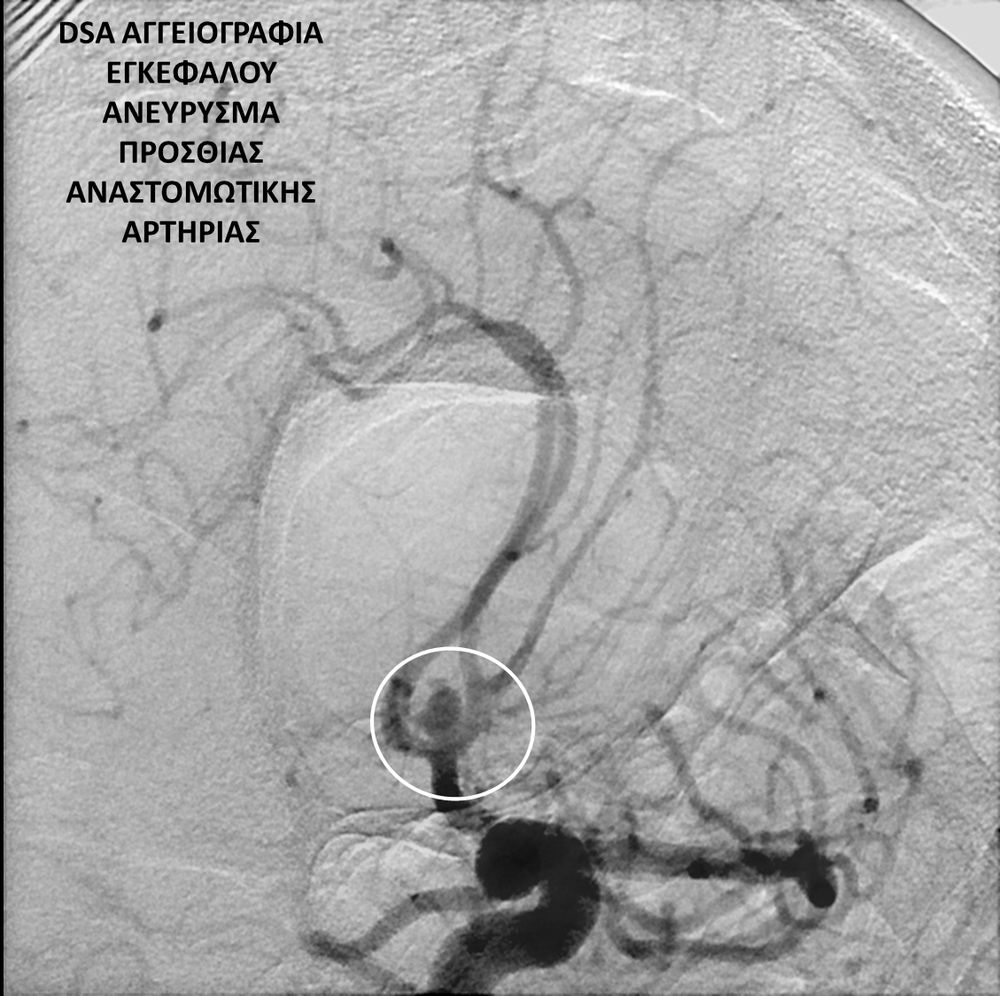

• Η ψηφιακή αγγειογραφία (DSA) αποτελεί την καλύτερη μέθοδο διάγνωσης των αγγειακών παθήσεων.Η αγγειογραφία γίνεται ως εξής: αρχικά παρακεντάται μια αρτηρία πρόσβασης, όπως η μηριαία αρτηρία στη βουβωνική περιοχή ή η βραχιόνια αρτηρία στο βραχίονα. Στη συνέχια προωθείται ένας καθετήρας προς την περιοχή του ενδιαφέροντος και γίνεται η έγχυση σκιαγραφικής ουσίας (σκιαγραφικού) με συνεχή λήψη «εικόνων» των αγγείων-στόχων.